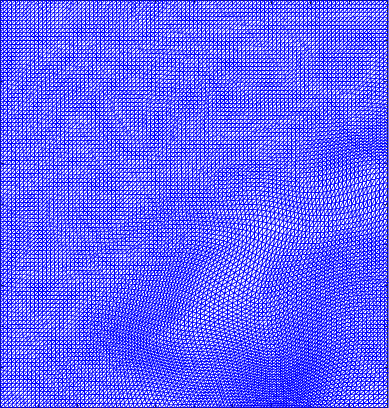

Figure 4 shows the visualisation of Figure 3 mappings in the form of grids. Let and be the Beltrami coefficients of the registration maps from the reference frame to the ground truth frame in Figure 3(a) and the perturbed frame in Figure 3(b) respectively. Figure 4(a) shows the mapping associated to Beltrami coefficient , and Fig 4(b) shows the mapping associated to BC . From Figure 4(c) and Fig 4(d), we can see that our method successfully restored the normal and abnormal deformation. Figure 4 serves as evidence that our decomposition is meaningful, in the sense that our method does not blindly return a Beltrami Descriptor with certain periodicity, but the decomposed descriptor does carry our desired information to recover the deformation to a large extent.